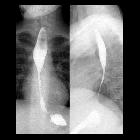

with long standing dysphagia and no other significant history. AP (left) and lateral (right) images from an upper GI exam show a fixed, smoothly tapered, concentric, long narrowing of the esophageal lumen of the mid to distal esophagus.The diagnosis was congenital esophageal stenosis.